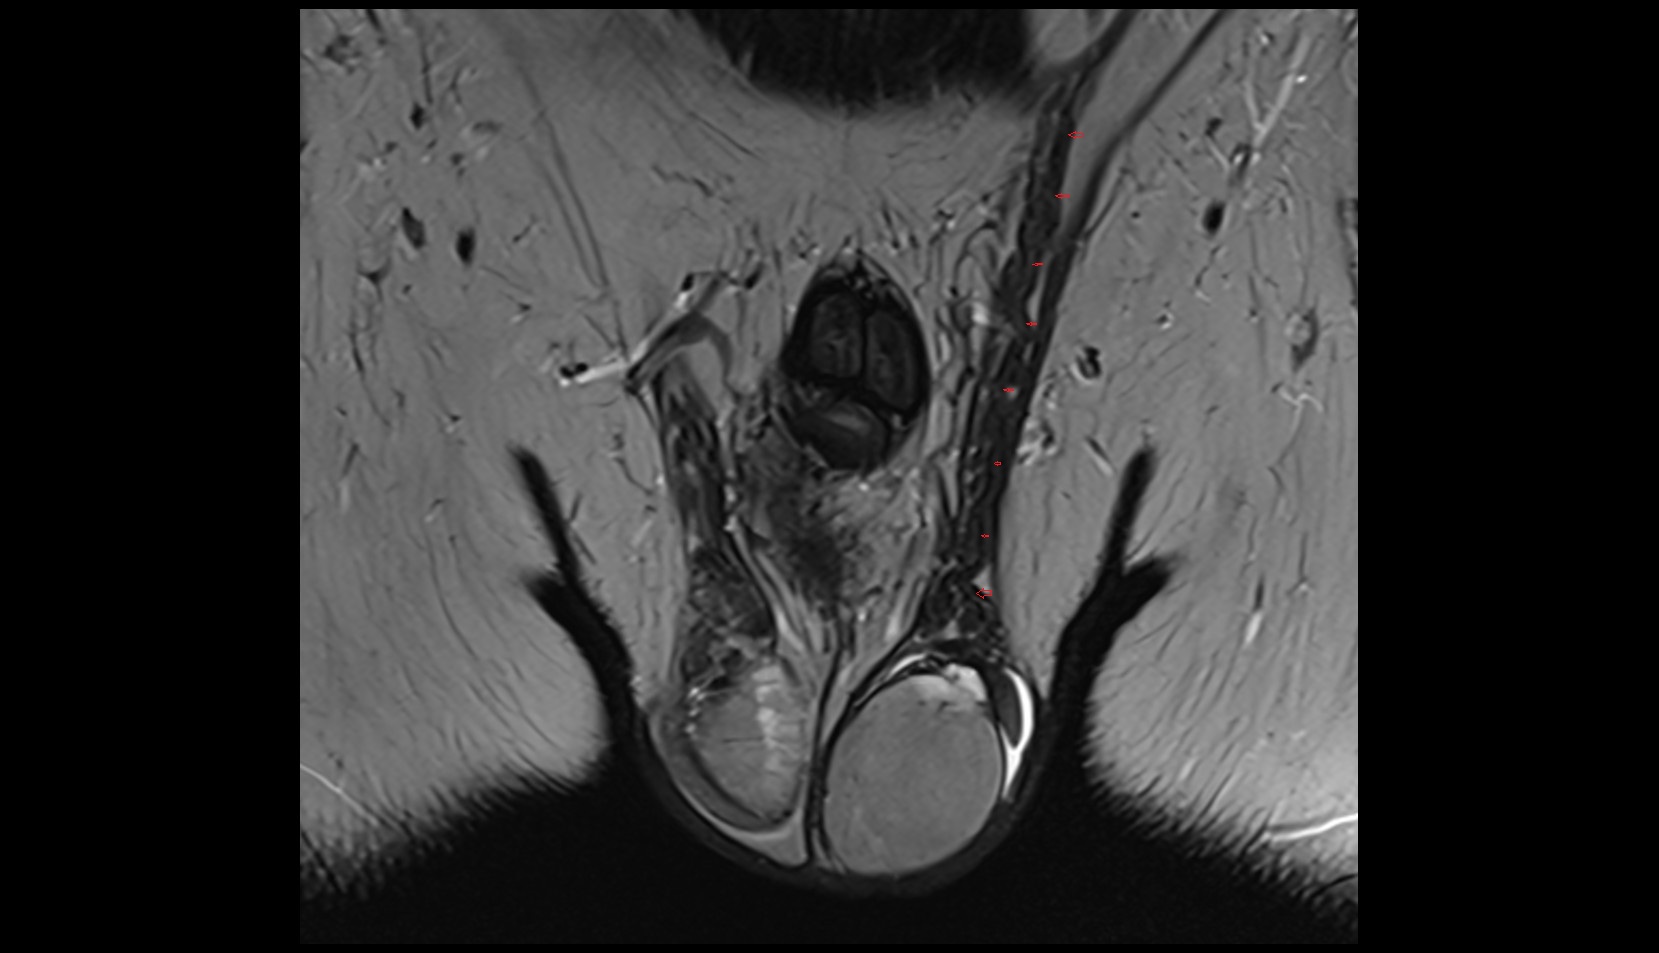

- Corpus cavernosum

- Corpus spongiosum

- Bulb of Penis

- Crus of penis

- Testis

- Tunica albuginea (penis)

- Tunica albuginea of testis

- Septum of scrotum

- Skin of scrotum

- External spermatic fascia

- Cremaster fascia

- Internal spermatic fascia

- Parietal tunica vaginalis

- Lobule of testis

- Mediastinum testis

- Visceral tunica vaginalis

- Scrotal fluid

- Septum of testis